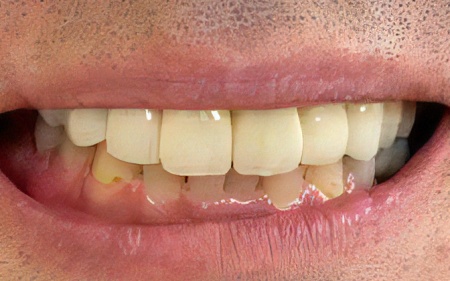

治療前

治療後